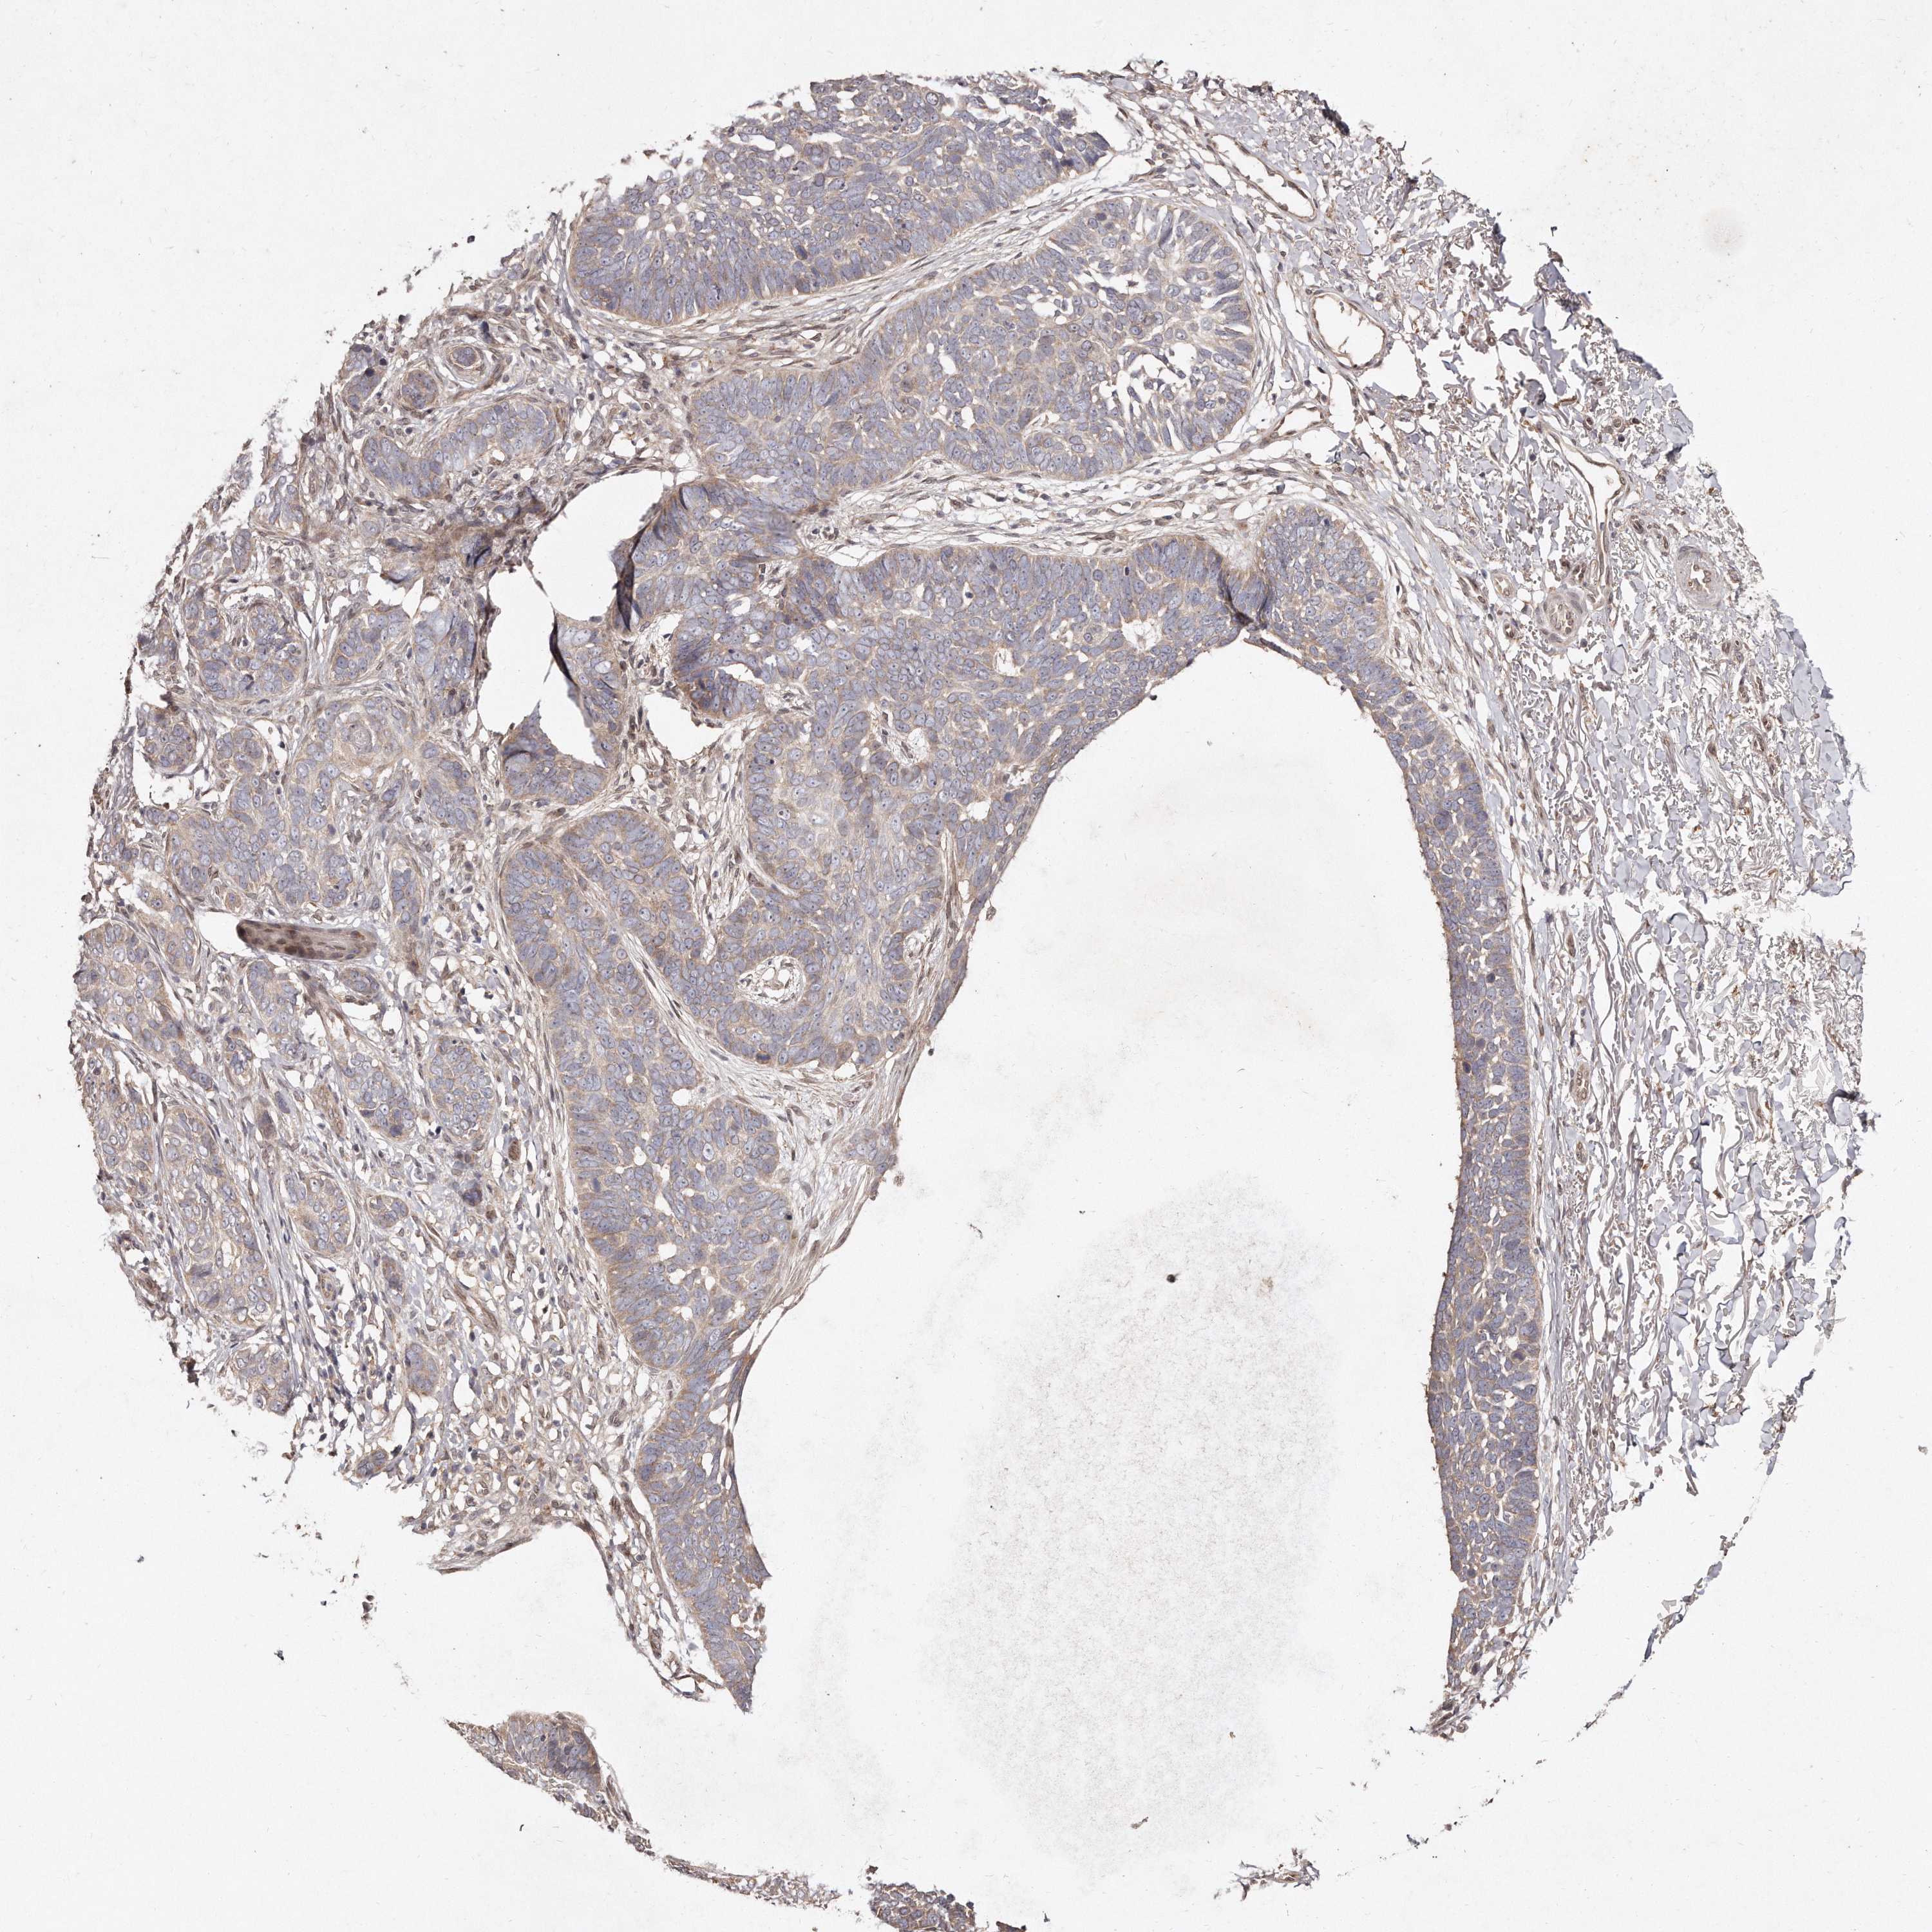

SKIN CANCER - Protein expressioni

A mouse-over function shows sample information and annotation data. Click on an image to view it in a full screen mode. Samples can be filtered based on level of antibody staining by selecting one or several of the following categories: high, medium, low and not detected. The assay and annotation is described here.

Antibody stainingi

Antibody staining in the annotated cell types in the current human tissue is reported as not detected, low, medium, or high, based on conventional immunohistochemistry profiling in selected tissues. This score is based on the combination of the staining intensity and fraction of stained cells.

Each image is clickable and will lead to virtual microscopy that enables deeper exploration of all samples and also displays staining intensity scores, fraction scores and subcellular localization as well as patient and tissue information for each sample.

Antibody HPA027422

Squamous cell carcinoma, NOS